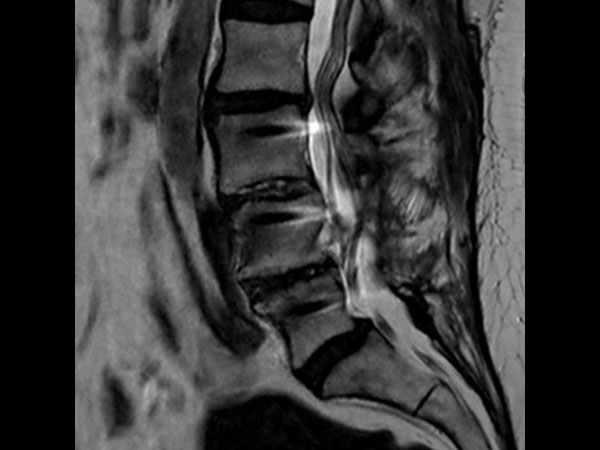

Lumbar Spine with metal implant, routine and fast

Utrecht Medical Center, The Netherlands

**Only for use with MR Safe or MR Conditional Implants by strictly following the Instructions for Use.